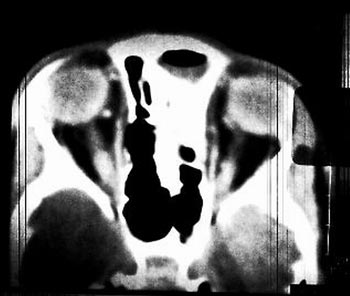

ρινικά) και ημιπάρεση αριστερά. Η επανεκτίμηση της CT εγκεφάλου έδειξε εκτός

από σημεία ηθμοειδίτιδας και μετωπιαίας κολπίτιδας (εικόνα 1) και πιθανή συλλογή

υγρού στην μεσοημισφαιρική σχισμή (εικόνα 2). Στην αγωγή προσετέθη κλινδαμυκίνη

Εικόνα 2. CT (1o 24ωρο):

Πιθανή συλλογή υγρού στην μεσοημισφαιρική σχισμή.